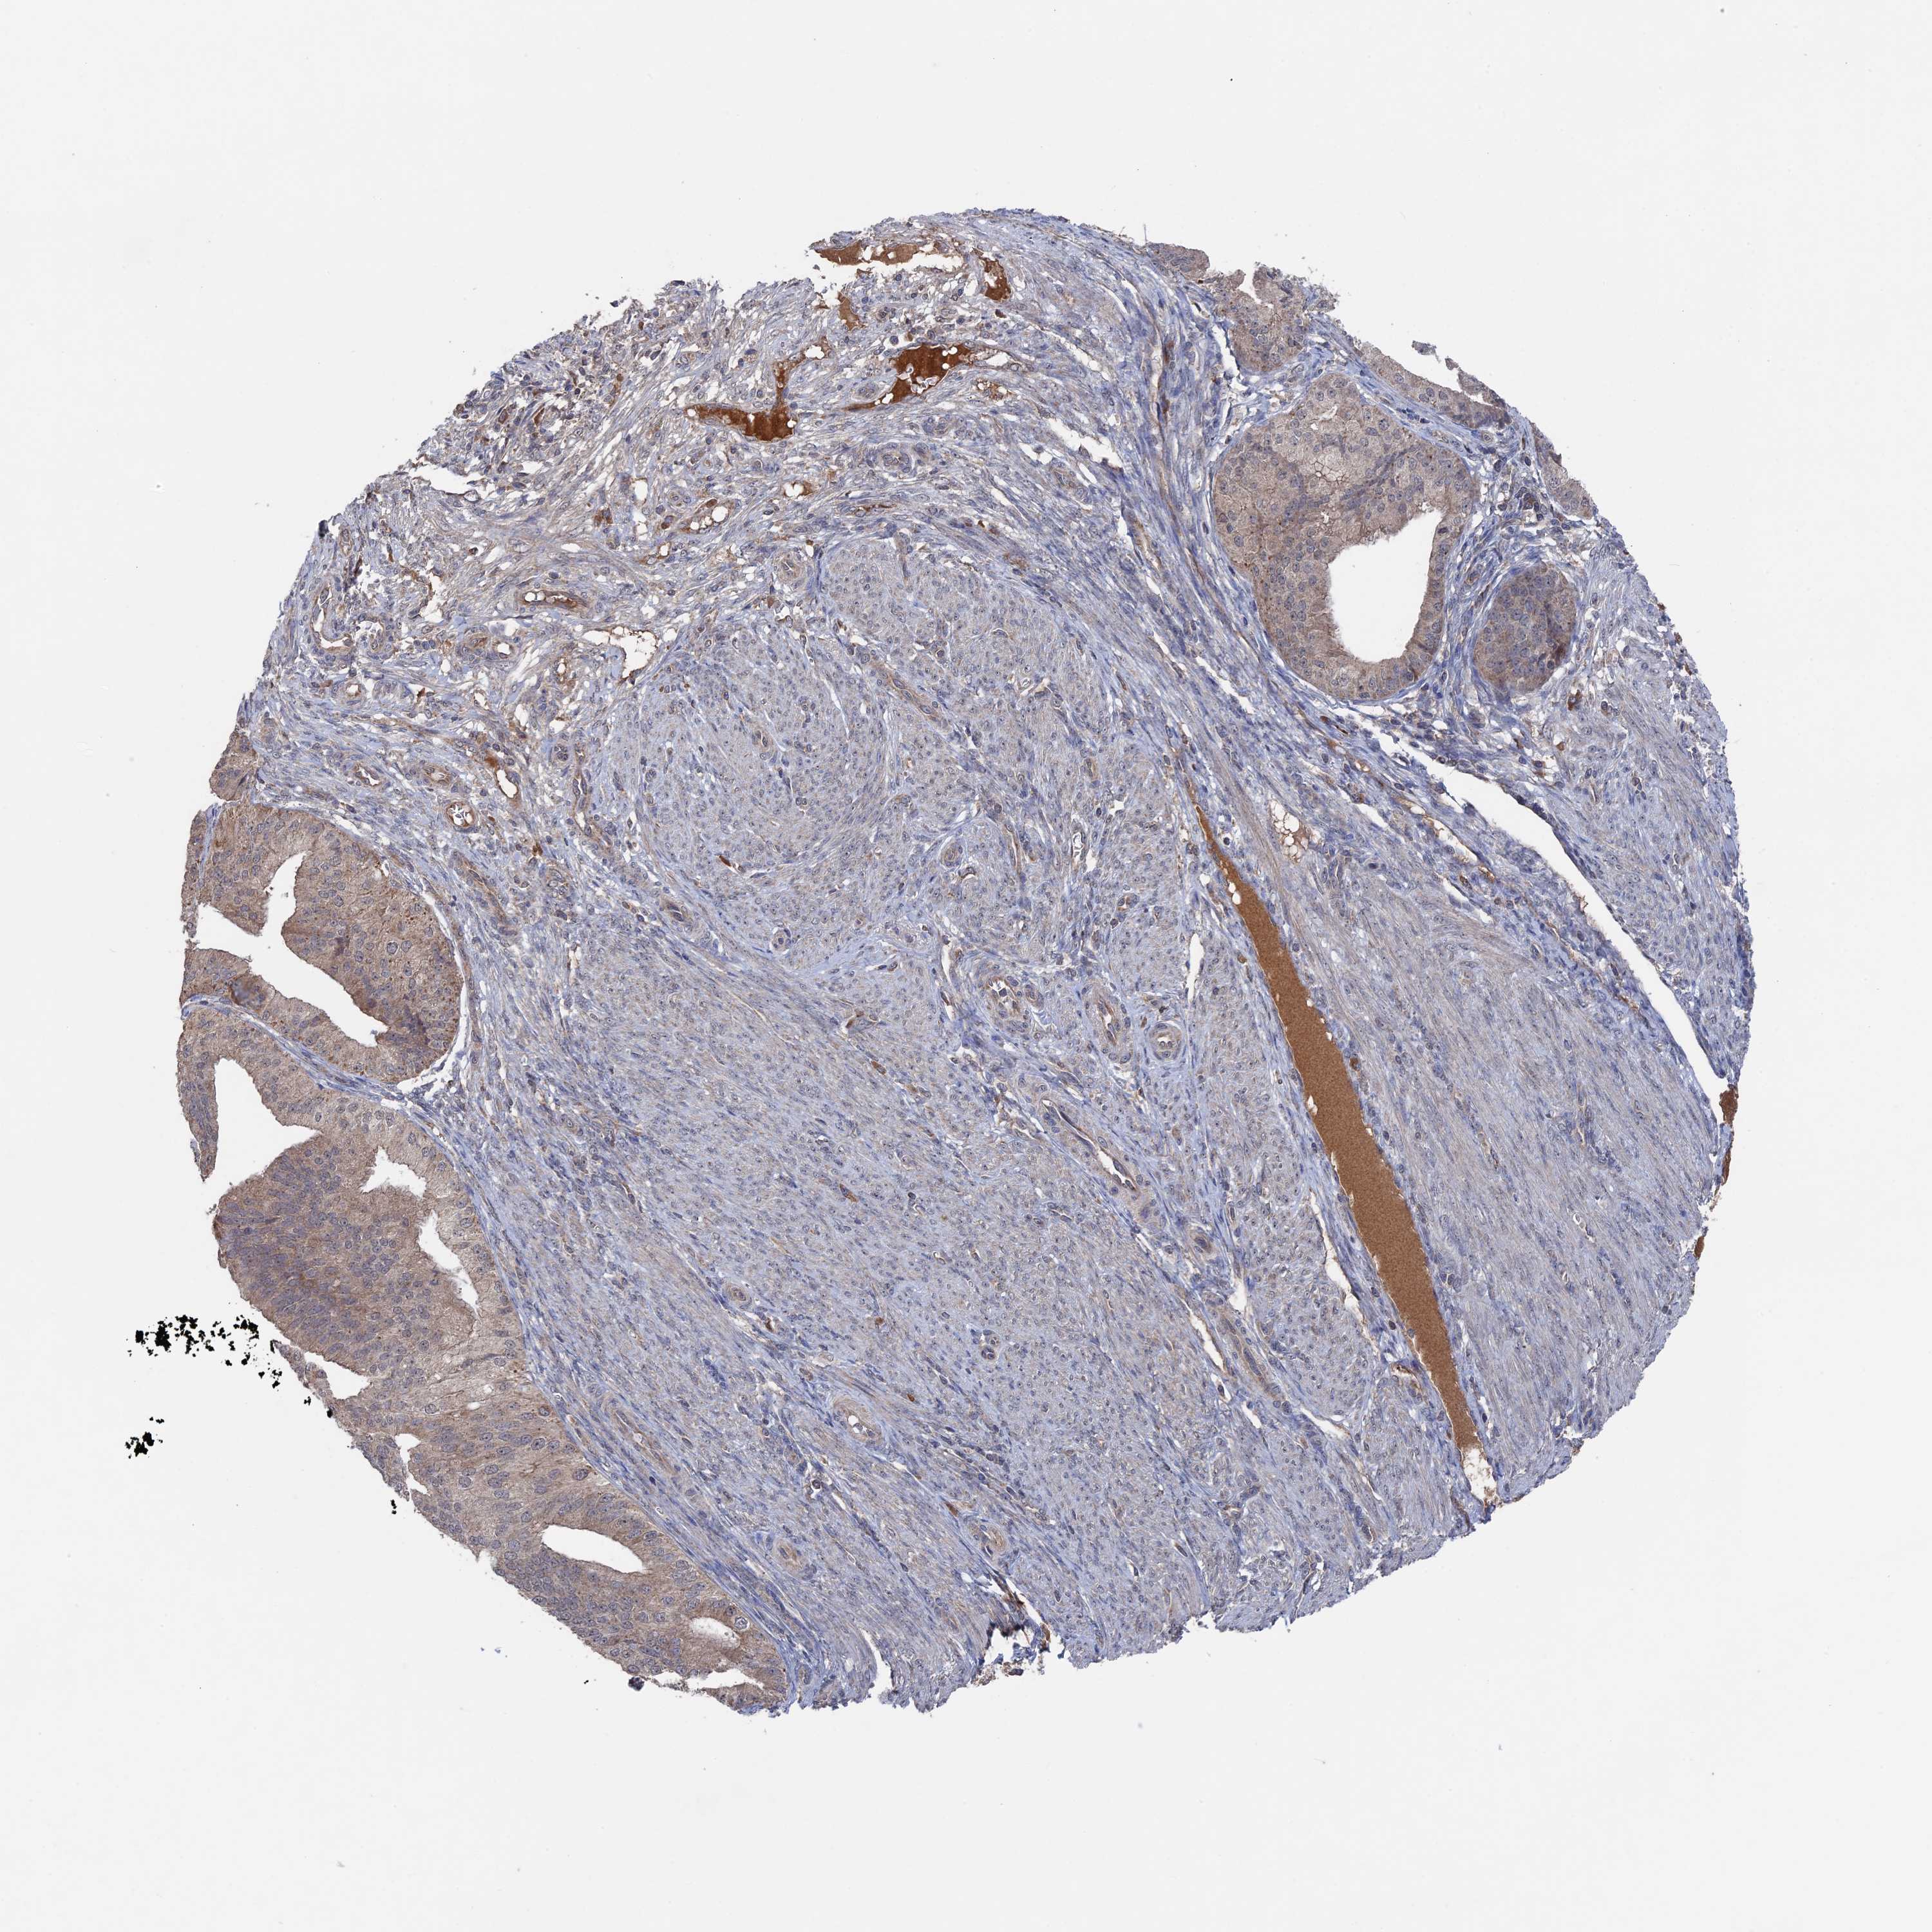

ENDOMETRIAL CANCER - Protein expressioni

A mouse-over function shows sample information and annotation data. Click on an image to view it in a full screen mode. Samples can be filtered based on level of antibody staining by selecting one or several of the following categories: high, medium, low and not detected. The assay and annotation is described here.

Note that samples used for immunohistochemistry by the Human Protein Atlas do not correspond to samples in the TCGA dataset.

Antibody stainingi

Antibody staining in the annotated cell types in the current human tissue is reported as not detected, low, medium, or high, based on conventional immunohistochemistry profiling in selected tissues. This score is based on the combination of the staining intensity and fraction of stained cells.

Each image is clickable and will lead to virtual microscopy that enables deeper exploration of all samples and also displays staining intensity scores, fraction scores and subcellular localization as well as patient and tissue information for each sample.

Antibody HPA041177

Staining

High

Medium

Low

Not detected

Intensity

Strong

Moderate

Weak

Negative

Quantity

>75%

75%-25%

<25%

None

Location

Nuclear

Cytoplasmic/membranous

Cytoplasmic/membranous,nuclear

Adenocarcinoma, NOS